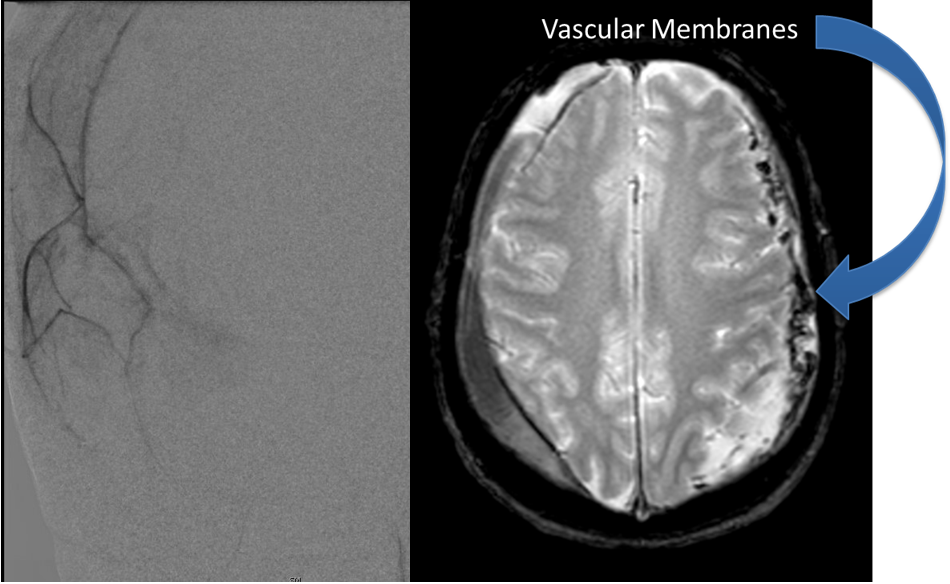

This is a 49-year-old otherwise healthy female who presented with bifrontal and retro-orbital headaches, behavioral changes, and forgetfulness. Symptoms have been progressively worsening over the past […]